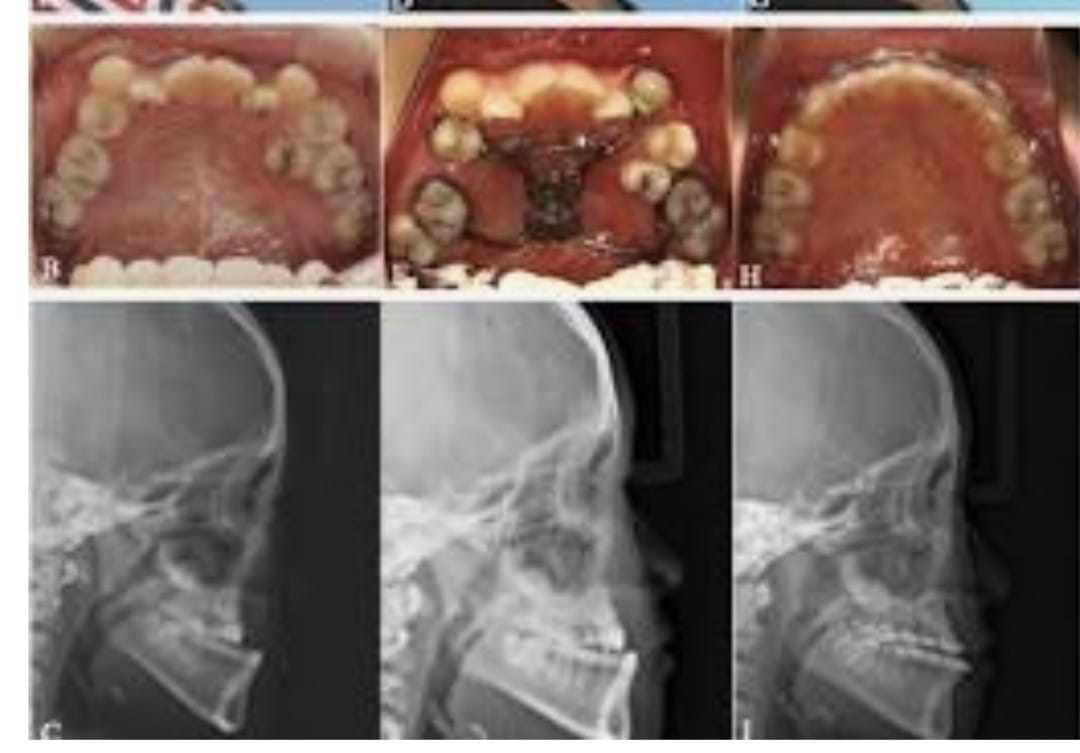

Maxillary hypoplasia is a condition characterized by the underdevelopment of the upper jaw (maxilla), which can affect both facial appearance and oral function. It often results in a sunken midface, improper bite alignment, and may contribute to breathing or speech difficulties. This condition can be congenital or develop during growth, impacting overall facial harmony and balance.

Treatment for maxillary hypoplasia focuses on correcting the position and structure of the upper jaw to improve both function and aesthetics. Depending on the severity, procedures such as orthognathic (jaw) surgery are performed to reposition the maxilla, enhance facial profile, and achieve proper bite alignment. With advanced surgical planning and modern techniques, patients can achieve improved facial balance, better oral function, and long-lasting results.